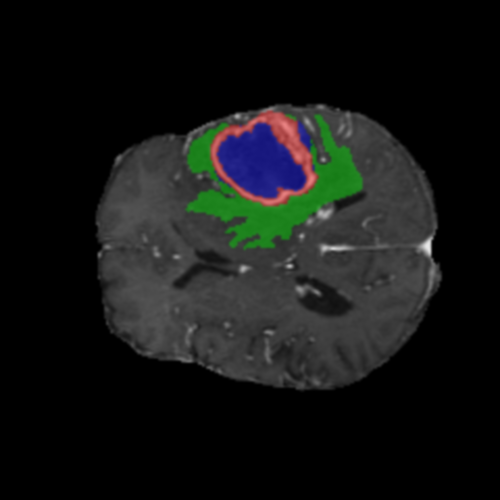

Mapas de Explicabilidad (Grad-CAM++)

Visualización de las regiones de atención del modelo que validan su razonamiento clínicamente relevante

Ejemplos HGG - Atención en Núcleo Necrótico y Tumor Realzado

HGG Grad-CAM++ 1 HGG Grad-CAM++ 2 HGG Grad-CAM++ 3 HGG Grad-CAM++ 4 HGG Grad-CAM++ 5 HGG Grad-CAM++ 6

Los heatmaps muestran que el modelo concentra su atención en las regiones de Tumor Realzado (rojo) y Núcleo Necrótico (azul), características patológicas clave de los gliomas de alto grado.